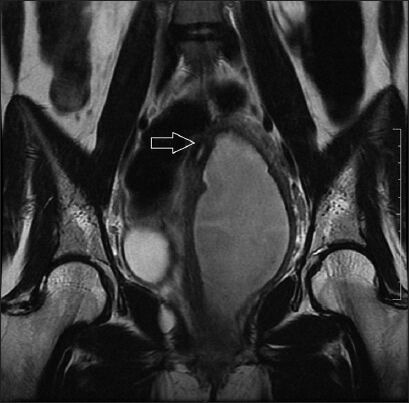

Obstructive mullerian anomalies give rise to a spectrum of clinical presentations and are uncommon in routine gynecologic practice. The patient usually becomes symptomatic in early reproductive years. Recurrent pelvic pain, dysmenorrhea, enlarging abdominopelvic mass, and abnormal vaginal discharge are the common presenting symptoms. We describe a rare case of a mullerian anomaly getting diagnosed 13 years after attaining menarche during the evaluation of postabortal sepsis. Patient presented 2 weeks following evacuation carried out for missed abortion, with acute abdominal pain, fever and foul smelling discharge per vaginum. The anomaly was identified as uterus didelphys with obstructed left hemivagina and ipsilateral renal agenesis (Herlyn-Werner-Wunderlich syndrome) complicated by pyocolpos. She was successfully managed by single-stage transvaginal septum resection under laparoscopic control.

Abstract Image